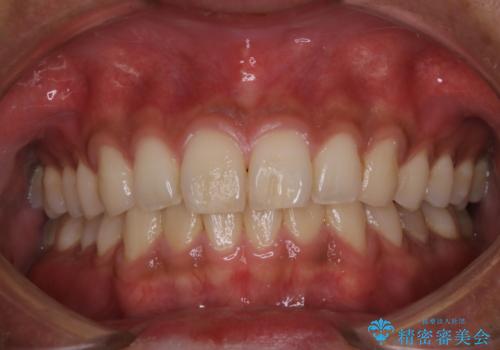

- 歯の色が気になるため、どの処置が適しているか相談してから施術をして欲しいとのことで来院されました。

全体的に汚れが付着していたため、まずはPMTCでご自身の本来の歯の状態にしてから、ホワイトニングにいついて考えましょうとなりました。

PMTCでは専門的な機械や材料を使用して、徹底的に汚れを除去するため、虫歯・歯周病・口臭予防などにつながります。